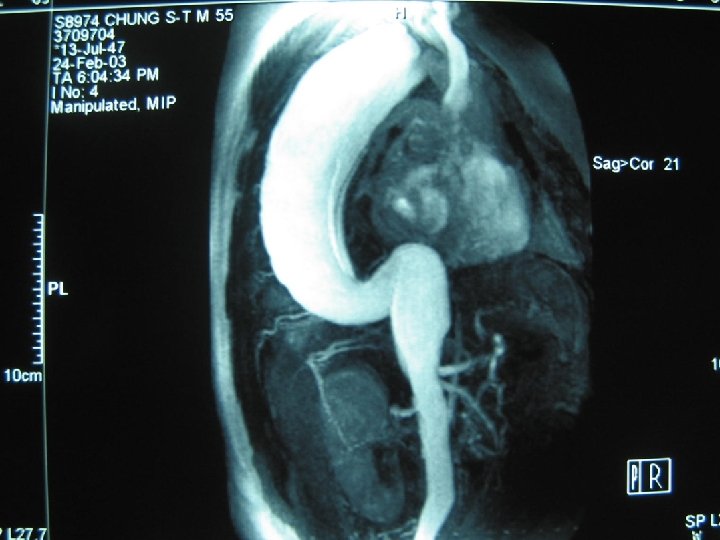

Case w 55 y/o male, HTN for 20+ years with regular medical control for 5 years w Chronic dissecting aortic aneurysm type III noted for 5 years w Left chest pain for 1 week w Denied other systemic diseases w Laboratory data: within normal range

Case w Normal screening spirometry w 2 -D echocardiography: dilated aortic root(diameter 63 mm) & LA, mild MR, good LV contractility w Planning: 1. Left post-lat thoracotomy 2. Femoralfemoral CPB 3. Hypothermia with circulation arrest and retrograde cerebral perfusion via high CVP 18~20 mm. Hg by femoral artery perfusion and partial clamp of venous drain tube 4. Restore proximal aorta perfusion after proximal anastomosis through graft cannulation 5. Open distal anastomosis

Case w Cooling to 16℃ w Partial bypass: 3 hr 25 min w Total bypass: 2 hr 30 min w Aortic cross clamp: ? min w Circulatory arrest: 20 min w Double lumen single-lumen ET tube ICU weaning and extubation on post-op day 3 without major complications